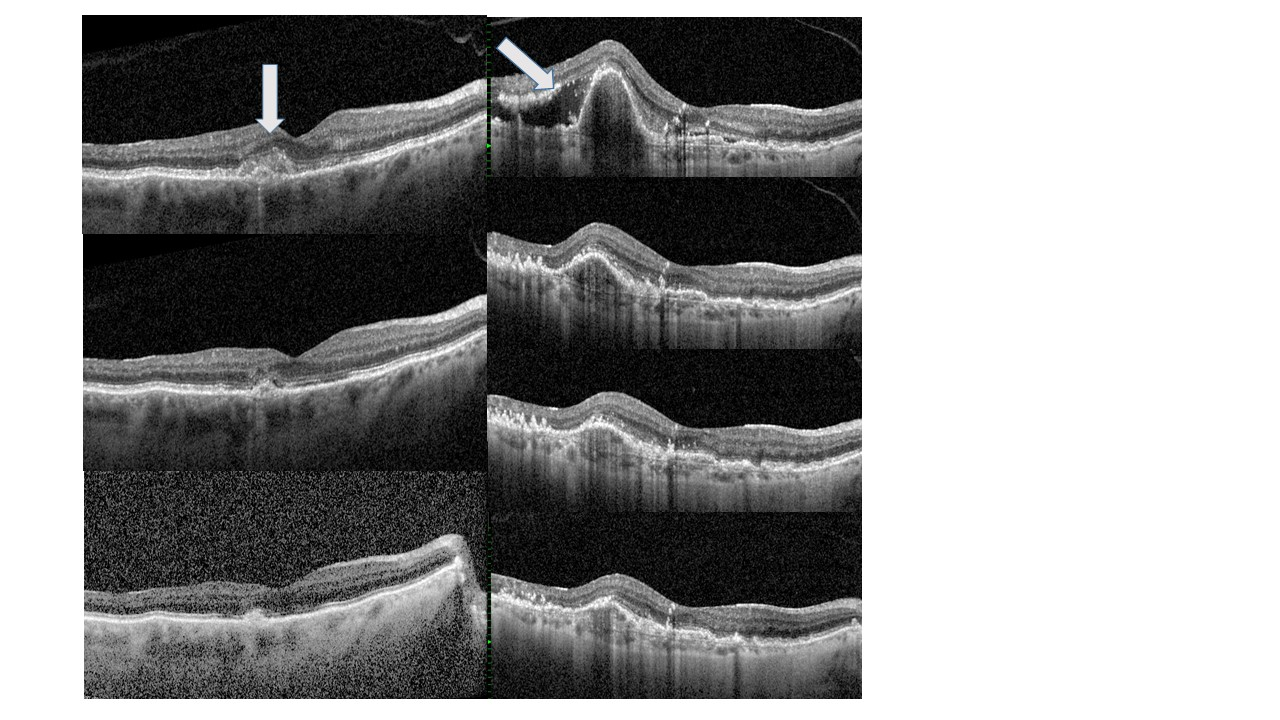

Let's start the discussion on how one can see if a drug works by giving an example - in the next blog post we'll talk more about the AVFs. In the photo below, the patient on the left has an early neovascularization - white arrow. These vessels regress or become smaller with subsequent injections (middle left and lower left). The same is true in the patient on the right. She has subretinal fluid (white arrow) and a retinal pigment epithelial detachment. Subsequent pictures shows the resolution of the subretinal fluid and the diminution of the RPE detachment.